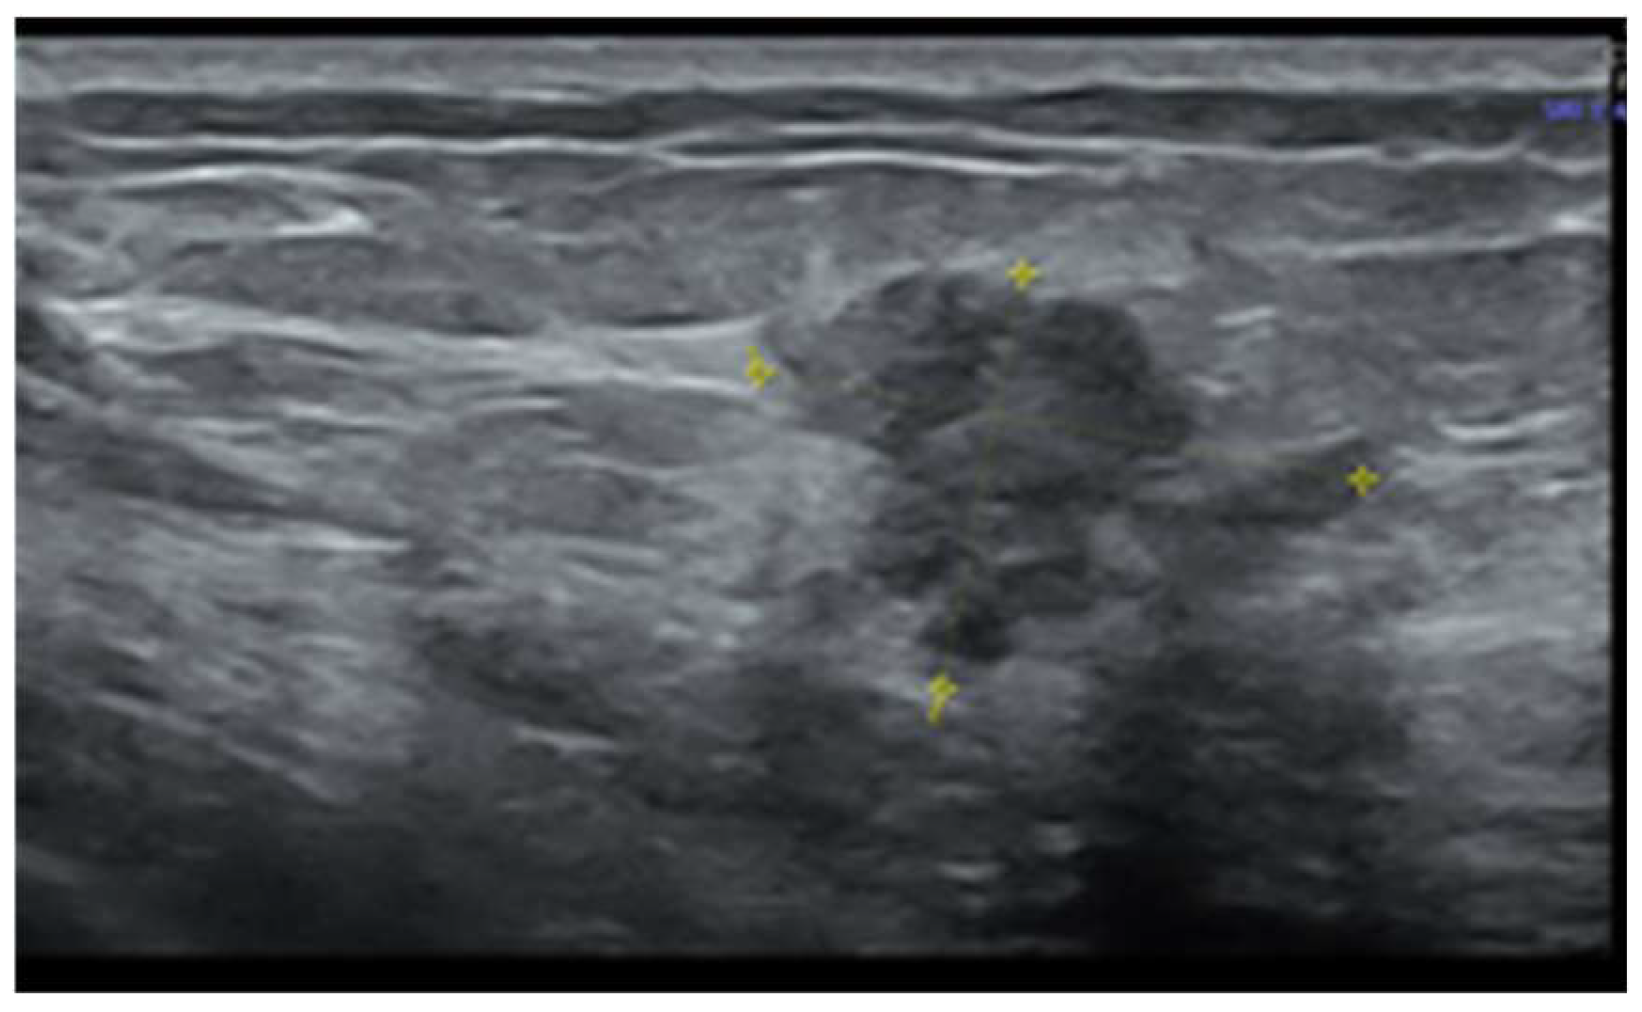

2. Case Report